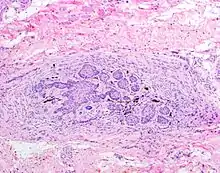

![]() The juxtaoral organ of Chievitz is composed of nests of benign squamoid epithelium closely associated with multiple nerve bundles. The deep location and squamous appearance can histologically mimic invasive squamous cell carcinoma. (Hematoxylin and Eosin stained section, 100x magnification) | |

The juxtaoral organ in humans is a small longish structure (10–14 mm in length, 1–2 mm in diameter), situated medially to the medial pterygoid muscle. The organ consists of a central ramified cord of epithelial parenchyma, embedded in connective tissue particularly rich in nerve fibers and sensory receptors. Close relations exist between epithelial cells and nerve endings. Histochemically, the parenchyma displays a characteristic pattern of various enzymes. Sporadically, epithelial follicles containing colloidal material can be found. The organ is surrounded by a dense, perineurium-like connective tissue.